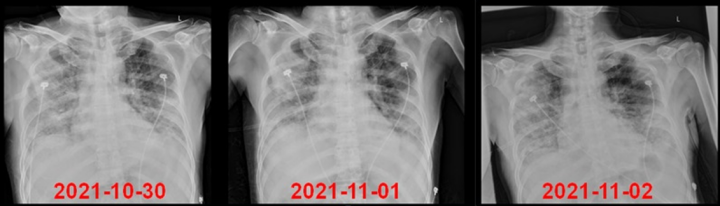

复查胸X线片如图4所示

4  复查患者胸部X线片情况